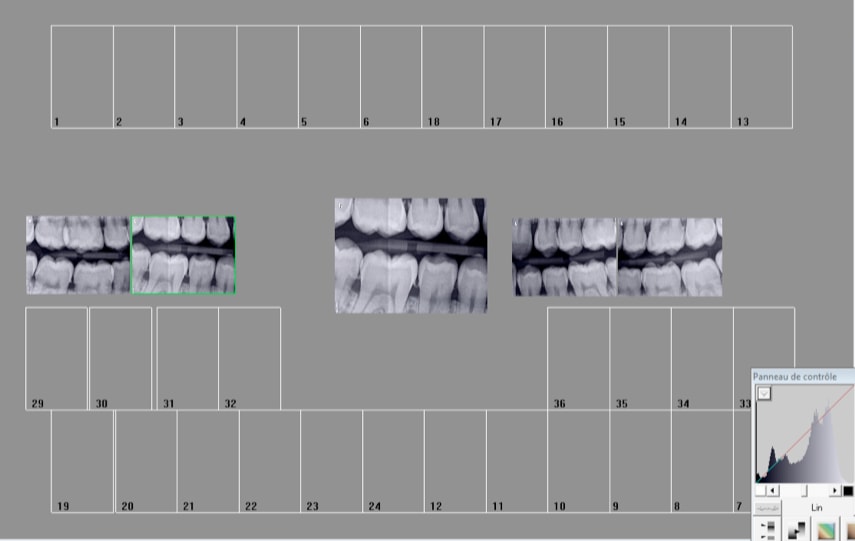

Quelle cotation pour ca sachant que :

1. Par dents contigües on entend : dents ayant des faces de contact mésiales et distales qu'il y ait diastème ou non.

2. Par secteur de 1 à 3 dents contigües on entend : secteur de 1 ou 2 ou 3 dents comprenant la dent sur laquelle est centré le cliché radiographique et chacune de ses dents adjacentes.

3. Facturation : quel que soit le nombre de clichés réalisés sur un même secteur de 1à 3 dents contigües. Ne peuvent pas être facturées pour un traitement endodontique.

Moi je vois 8 secteurs : HBQK142 Radiographies intrabuccales rétroalvéolaires et/ou rétrocoronaires de 8 secteurs distincts de 1 à 3 dents contigües

Qu'en pensez vous ?

En NGAP une rétrocoronaire correspondait à 2 secteurs ( car radiographie au singulier, pas justifiable d'en prendre 2 pour faire la meme chose) En CCAM il y a un code pour 8 secteurs sans préciser le nombre de radios nécessaires pour les couvrir. Maintenant avec cette histoire de radio centrée sur la dent au centre du secteur je ne sais pas si avec 2 rétro coronaires ( avec des plaques king size) on peut coter 8 secteurs. Pourtant ca va dans le sens d'une moindre irradiation du patient.

Clichés centrés sur : 16 46 15 45 26 36 25 35 8 secteurs distincts.

Mortel non cette CCAM ? C'es cool ca répond à la question du sujet : quels numéro de dents coter pour les bite wings. Ben celles au centre des 2 secteurs distincts qu'on voit sur un bite wing. Logique. -)

sur ces 2 clichés je vois 2 fois 3 secteurs justifiables